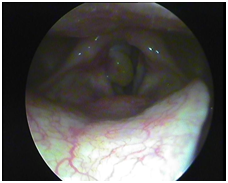

Post treatment size of granuloma has shrunken significantly with improvement in the voice .Patient has been further instructed to continue treatment for one month more.